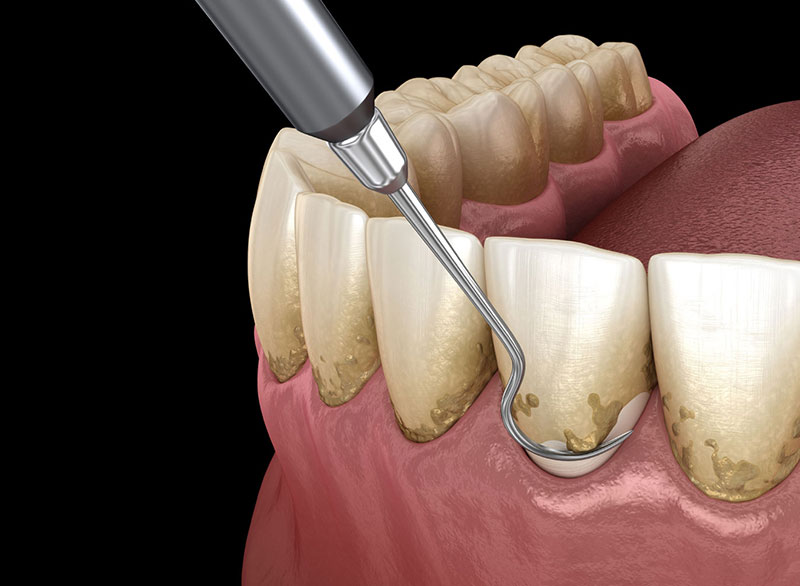

The removal of dirt on the teeth that is below the gums.